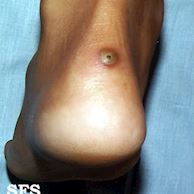

13

Q

Clinica tungiase:

A

Papula amarelada dolorosa com ponto escuro central

How well did you know this?

Tratamento tungiase

Enucleação com agulha+exerese

Se multiplas: tiabendazol 25mg/kg